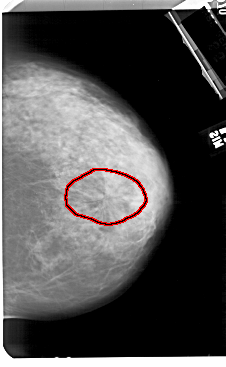

A_1504_1.LEFT_MLO

LEFT_MLO LINES 5491 PIXELS_PER_LINE 3631 BITS_PER_PIXEL 12 RESOLUTION 43.5 NON_OVERLAY

FILE: A_1504_1.RIGHT_MLO.OVERLAY

TOTAL_ABNORMALITIES 1

ABNORMALITY 1

LESION_TYPE MASS SHAPE ARCHITECTURAL_DISTORTION MARGINS SPICULATED

ASSESSMENT 5

SUBTLETY 3

PATHOLOGY MALIGNANT

TOTAL_OUTLINES 1

BOUNDARY